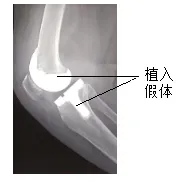

30.膝关节骨性关节炎患者的膝关节关节面受损,活动受限,且疼痛剧烈。膝关节置换手术通过植入假体可改善关节活动程度并可缓解疼痛。据图推测,植入的假体替换的结构是()

A.关节软骨和关节腔B.关节腔和韧带

C.关节头和关节窝D.关节软骨和关节头